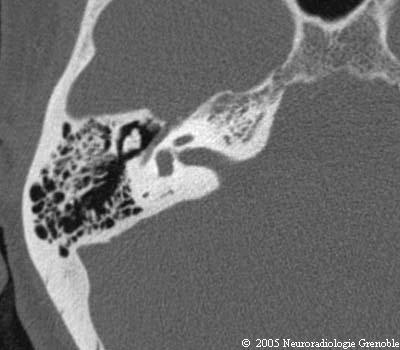

Radioanatomie TDM du rocher normal

Méat acoustique interne

Cochlée

Vestibule

Canal semi-circulaire postérieur

Aqueduc du vestibule

Marteau (tête)

Enclume (corps)

Canal du facial (2ème portion tympanique)

Epitympan (attique)

Aditus ad antrum

Cellules mastoïdiennes

Antre